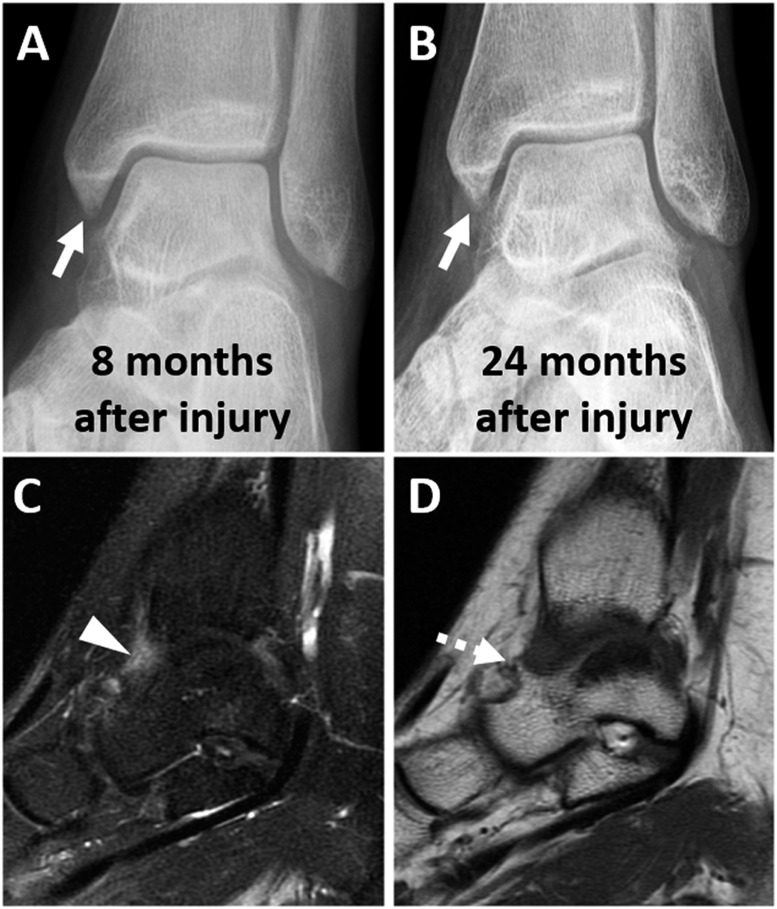

图8。

一名20岁女性,有踝关节扭伤病史,前内侧疼痛逐渐加重,背屈受限,与前内侧撞击相一致:(A,b)损伤后8个月和24个月的斜位片显示内踝前丘的骨增生逐渐增大(箭头所示)。(c) 矢状位液体敏感序列和(d)矢状T1加权序列显示前内侧隐窝(箭头)和邻近骨赘(虚线箭头)有滑膜炎。